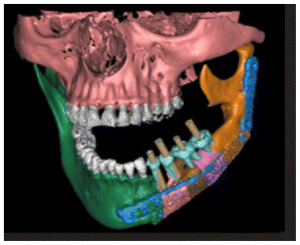

Due to the size of the lesion a mandibular titanium rod was placed to preserve the the lower portion of the mandible and part of the ascending ramus and condyle of the mandible (Figures 6,7,8) In the panoramic rx, the placement of the titanium rod can be seen to fix the ascending ramus with the condyle and the right side of the mandible with the resection to the level of the left lower canine (Figure 9).

Subsequently, a Walter Lorenz Titanium mesh (Figure 10,11) was used to contain the autologous bone that was obtained from the anterior iliac crest mixed with BMP2 morphogenetic protein (Cowell PLUS BMP), as well as Alogen bone mixed with growth factors and membranes with the Chuckron technique (Figure 12, 13,14)

The patient after surgery continued under observation and could not continue with her treatment due to the Covid epidemic, resuming the treatment on 03/02/2014 for the reassessment by CT the new bone formed in the area of surgery was observed by two programs Blues Sky Bio and Mimics of Materialise the values in Hounsfield units were determined in each of the CT slices at the sites planned for the placement of three implants, the values ranged from 209 U. Hounsfield to 1372 U. Hounsfield (Figs, 15,16,17,18).

In the CT scan, the bone regeneration of the morphogenetic protein BMP2 (Cowell PLUS BMP) and the growth factors with the Chucron technique were verified, managing to observe a good bone conformation, however, a bone formation was observed towards the upper part of the jaw that did not follow any anatomical pattern of the mandibular body and was attached to the mandibular body. (Figures 19,20, 21)